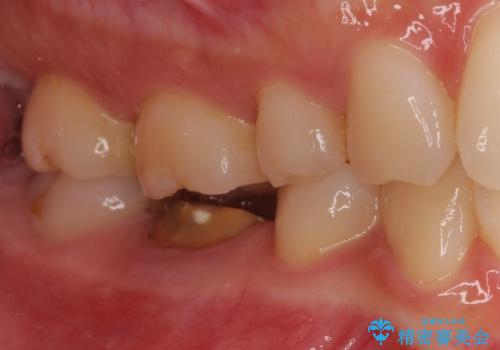

- セラミッククラウンが破損したため、職場近くのクリニックで治療開始したものの、当院への転院を希望して来院された患者様です。

クラウン再製作の際、提案された根管治療を開始したものの、処置の度に痛みを感じるとのことでした。

当院にて根管治療を行った後に、フルジルコニアクラウンにて補綴することとしました。

前医での根管治療の度に感じていた痛みの原因は分かりませんでしたが、元々違和感すらなかった歯であったので、速やかに根管治療を行った後に、ジルコニアクラウンを装着しました。

咬み合わせが強く、歯の高さが非常に低かったため、審美性には劣るものの、高強度であるフルジルコニアクラウンを採用しました。